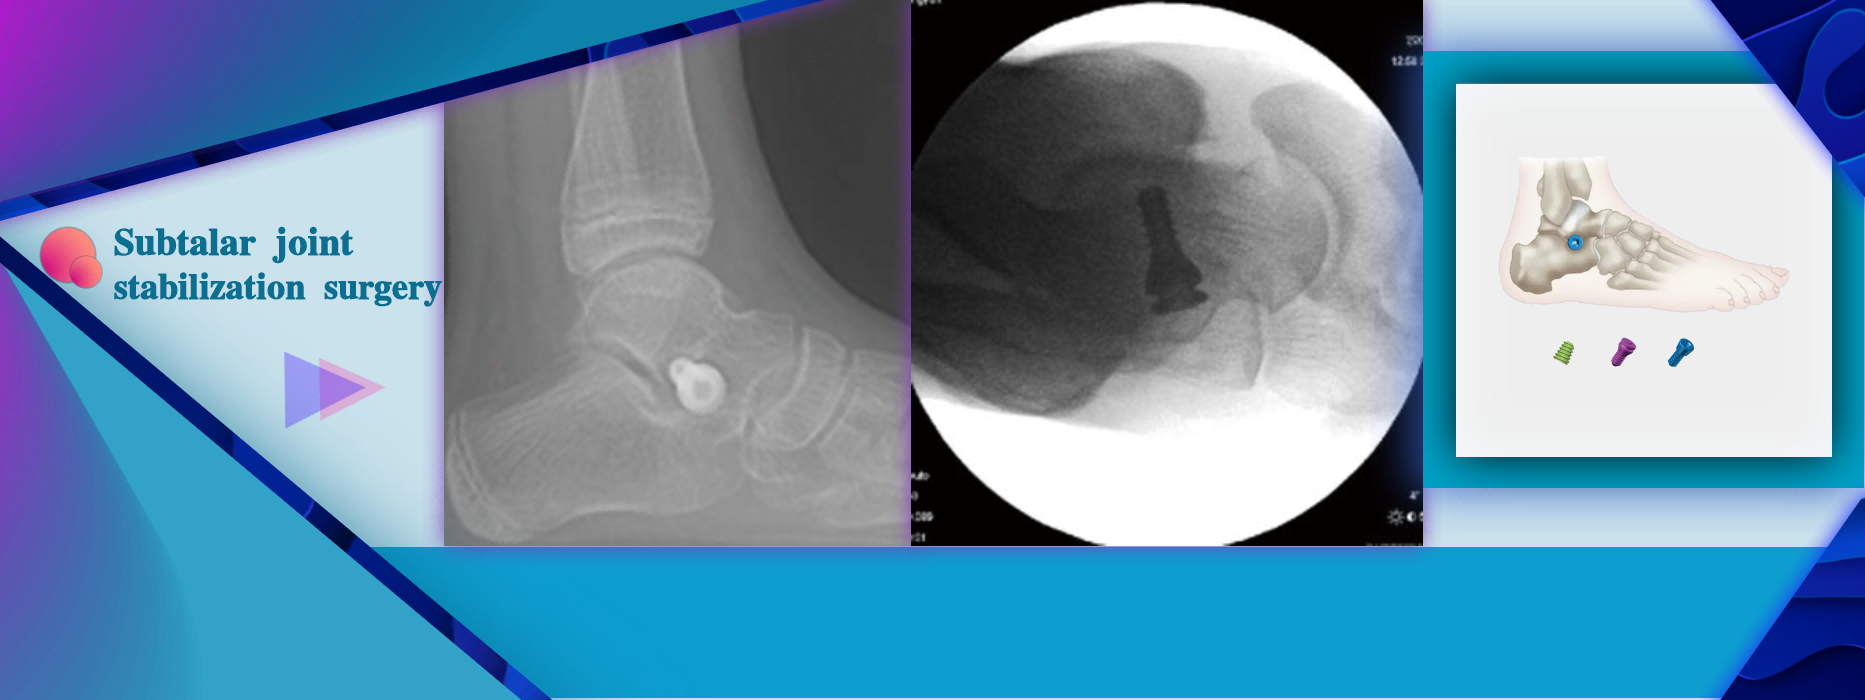

More InformationFlexible flat feet (children, adolescents, adults) Merge flat feet with navicular bone disease Spasmodic paralysis type flat foot (dysfunction of the posterior muscle tendon) Valgus deformity of hind foot Dislocation or instability of the subtalar joint

Flexible flat feet (children, adolescents, adults) Merge flat feet with navicular bone disease Spasmodic paralysis type flat foot (dysfunction of the posterior muscle tendon) Valgus deformity of hind foot Dislocation or instability of the subtalar joint